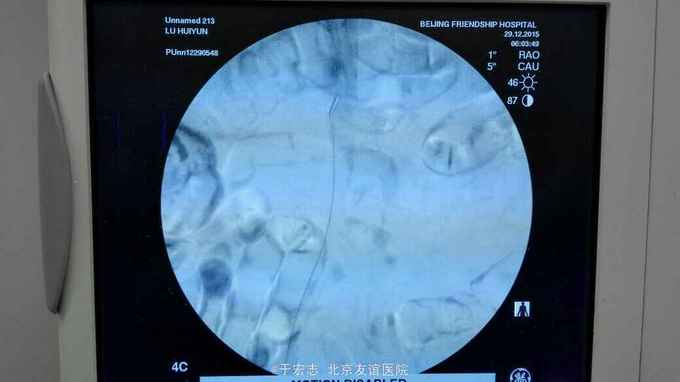

全腔内技术操作,用8F rotarex机械取栓导管操作,术前留置股静脉鞘,边操作边放静脉血,减少毒素吸收。静脉血经自体血回收处理。 操作完成后以血管缝合器缝合股动脉穿刺点,加压包扎。 患者转重症医学科途中出现心跳骤停,于手术室心外按压2小时复苏成功,转重症医学科血滤治疗。术后五小时生命体征均可维持,但家属还是放弃进一步治疗转运回当地治疗。